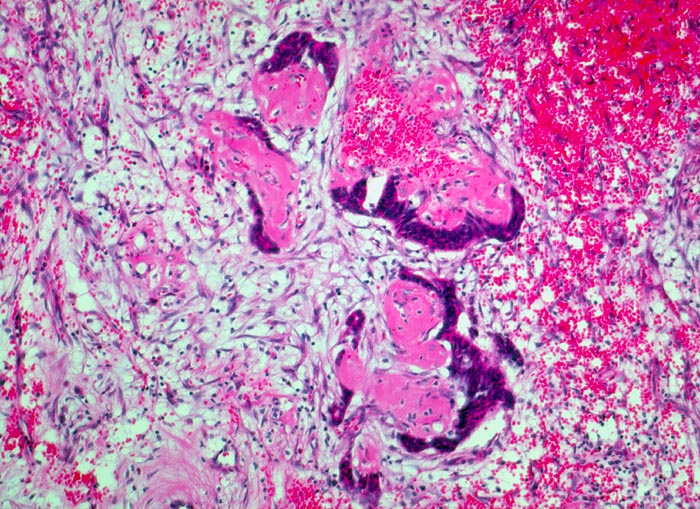

Intraduktales Papillom mit Dcis: Stichkanal nach Nadelbiopsie

Maschenwerk von Fibroblasten mit frischer Einblutung. Ins Maschenwerk eingebettet versprengte Anteile eines papillären Tumors (Stichkanal nach Nadelbiopsie).